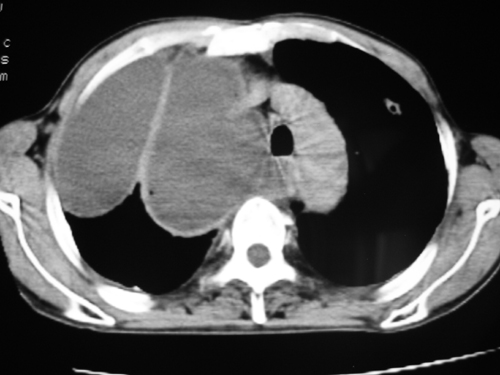

以下是引用yangyudong333在2008-4-29 5:46:00的发言:[br]1左上叶结节呈分叶状,边缘毛刺,考虑肺癌并纵隔淋巴结转移可能性大,结核待排,[br] [br]2右侧多发包裹性胸腔积液